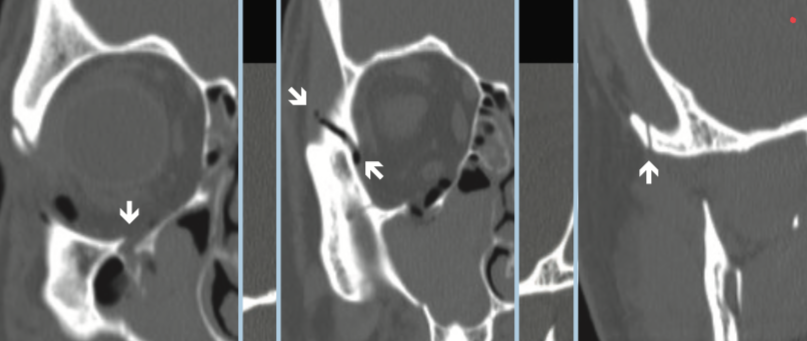

Naso-orbito-ethmoidal fracture. What to report on CT?

Naso-orbital-etmoidal fractures complications?

ORBITAL FRACTURES?

Orbital Apex fragments can lead to optic nerve damage